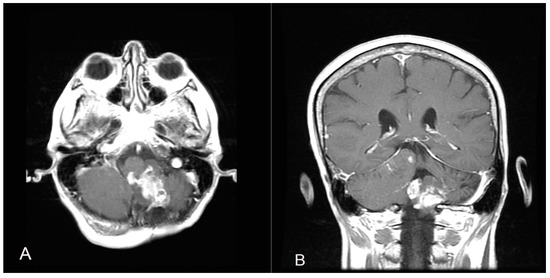

A 58-year-old woman presented with nausea, headache and gait instability. A brain contrast-enhanced magnetic resonance imaging (MRI) device documented an expansible lesion in the left cerebellar hemisphere involving the middle-lower cerebellar pedicle surrounded by perilesional edema (measures: transverse diameter: 3.2 cm; sagittal diameter: 3 cm). Compression of the IV ventricle and cerebellar tonsils herniation in the foramen magnum were present. Also, tri-ventricular obstructive hydrocephalus was present (Figure 2). The patient underwent ventricular shunt and microsurgical exeresis of the lesion via left suboccipital craniectomy (Figure 3). The histopathological examination documented a grade I glioneuronal lesion. After the first operation, the patient underwent adjuvant radiotherapy treatment with a total of 54 Gy in 27 sessions, with daily fractionation of 2 Gy/day. Clinical and radiological follow-up was then recommended.

Figure 2.

Axial (A), sagittal (B) and coronal (C) T1 contrast-enhanced weighted brain MRI shows a lesion in the left cerebellar hemisphere involving the middle-lower cerebellar pedicle surrounded by perilesional edema and tri-ventricular obstructive hydrocephalus for compression of the IV ventricle.